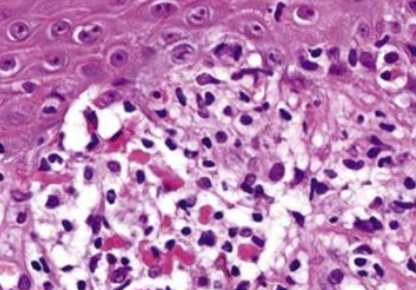

水皰期

上皮內裂解,內部充滿嗜酸性球

疣狀期

過度角化, acanthosis, papillomatosis

色素過度沉積階段

皮下結締組織 melanin-containing macrophage,即黑色素失調(melanin incontinence) alt text